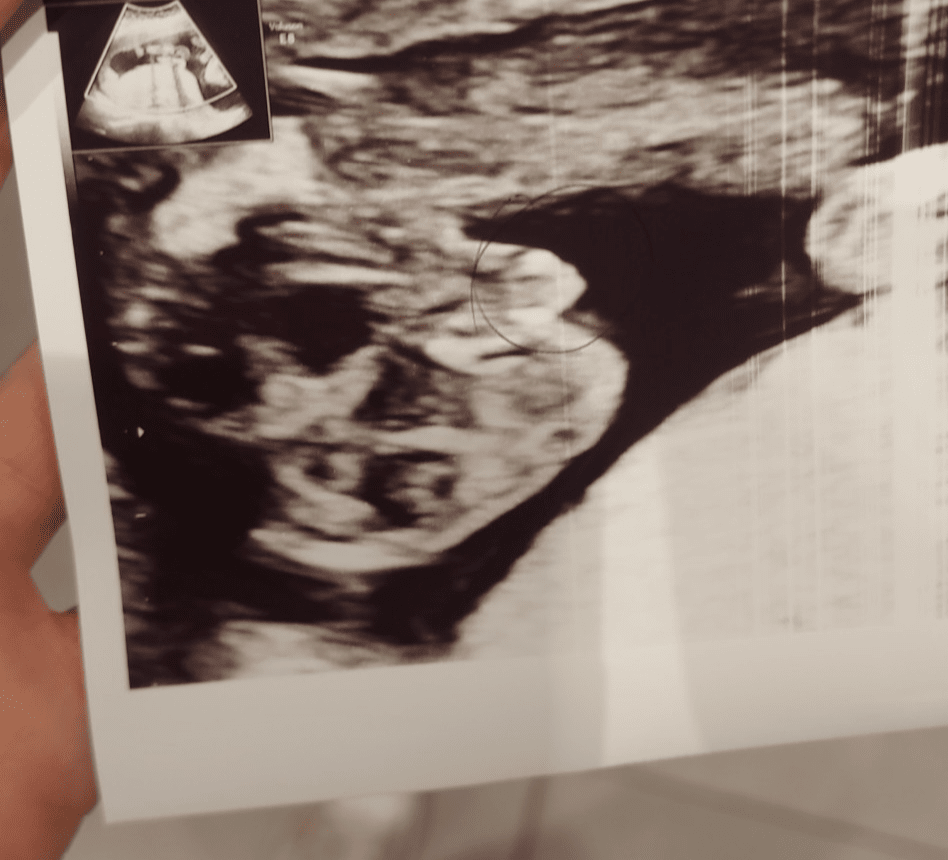

Hej dziewczyny jak myślicie kto to ? Doktor na 1 prenatalnych obstawiała dziewczynkę, teraz 16tc na zdjęciu mówi, że może być chłopiec ale również dziewczynka tylko z opuchniętymi wargami. Za 3 tyg wizyta ale ciężko wytrzymać, jak sądzicie ?![]()